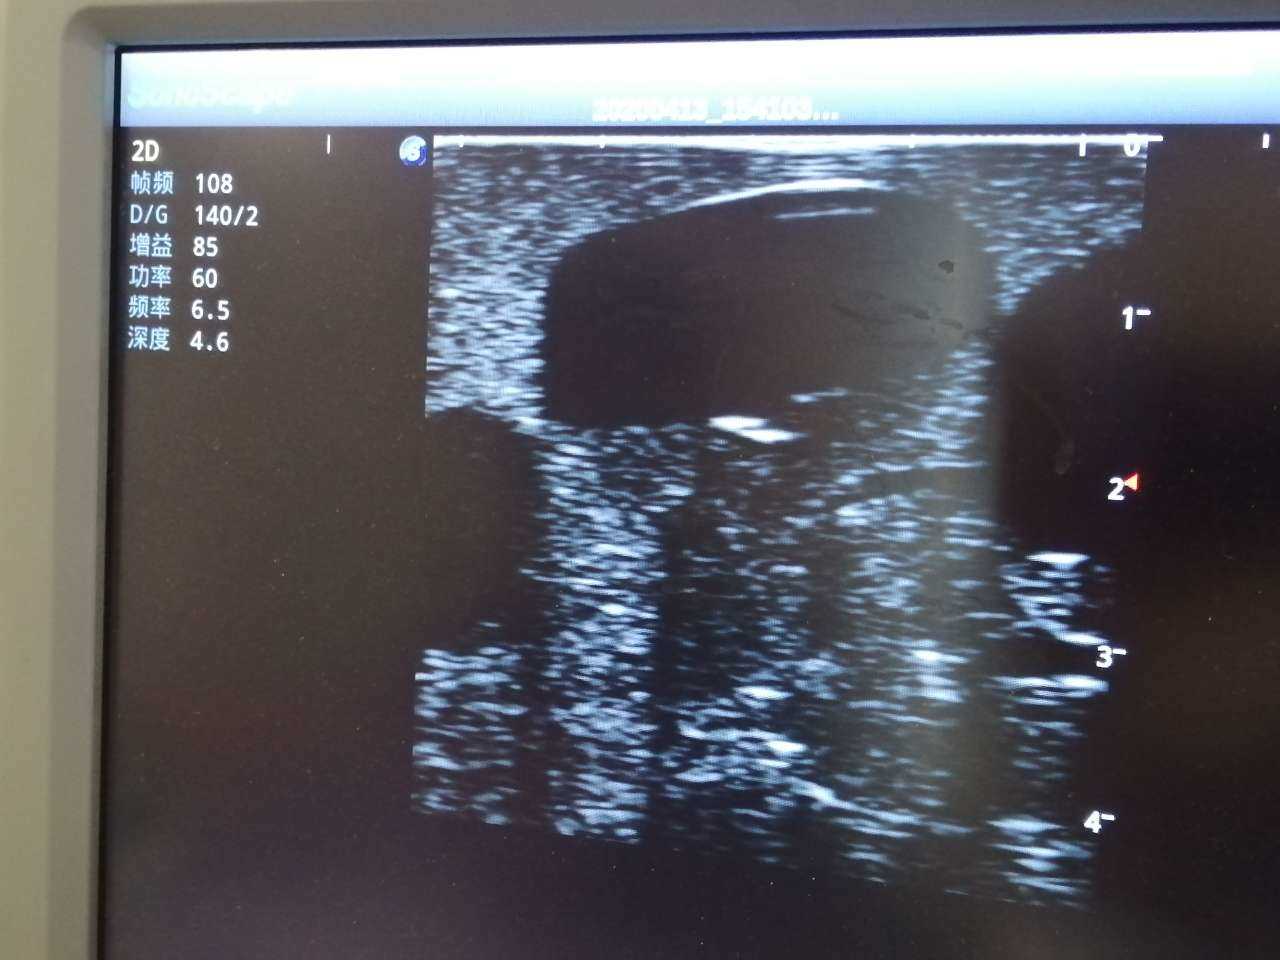

· High-quality ultrasound images to show skin, soft tissues, abscess cavity and pus